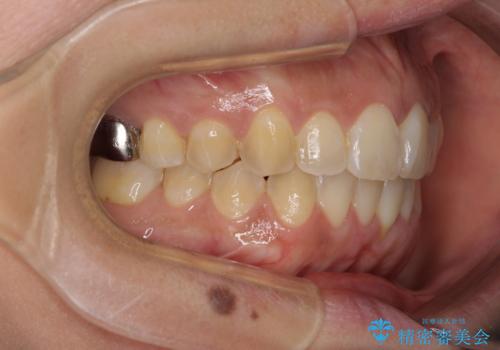

インビザラインによる狭窄歯列の拡大矯正

- 前歯のデコボコを治したいとのことで来院された患者様です。

上下顎ともに歯列全体の後方移動と側方拡大、IPR(歯と歯の間を削る)によってデコボコが解消するように設計し、インビザラインにより治療を行うこととしました。

後方移動に際し、上下の親知らずは4本とも抜歯することとしました。